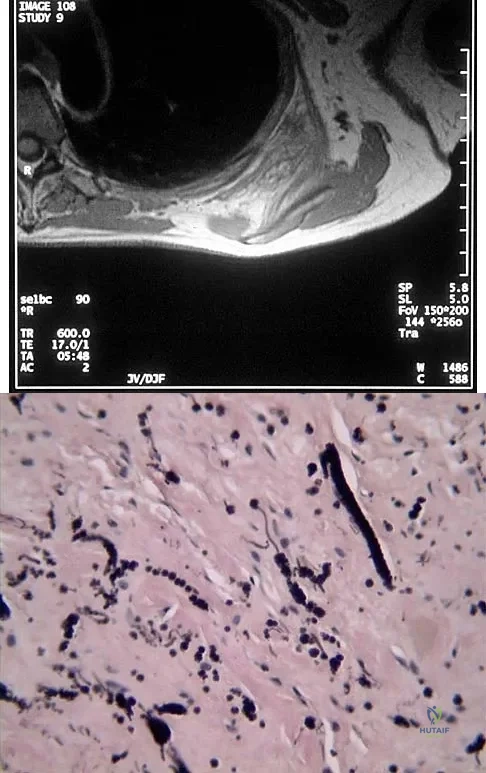

A 9-year-old girl reports progressive right knee pain. Radiographs are shown in Figures 59a and 59b. Work-up reveals no other sites of disease. Low- and high-power photomicrographs are shown in Figures 59c and 59d. What is the most appropriate treatment?

Explanation